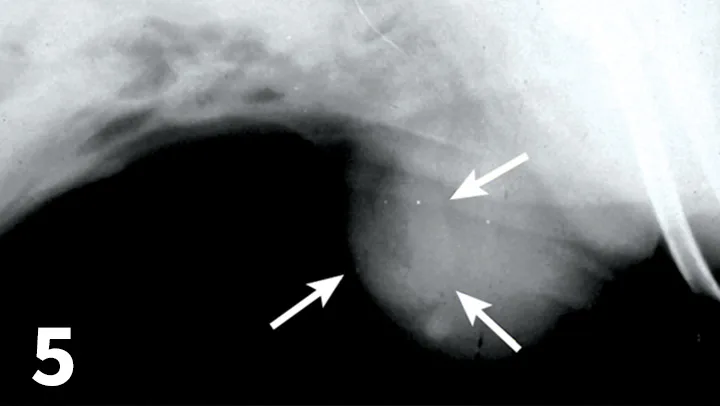

Featured Image

FIGURE 6

Ultrasound reveals a focal defect within the linea alba (arrows). Intra-abdominal fat extends through the defect into the subcutaneous tissues.

• CT and ultrasound may help differentiate a fluid pocket from presumed cellulitis or help locate an abdominal wall defect (Figure 6).